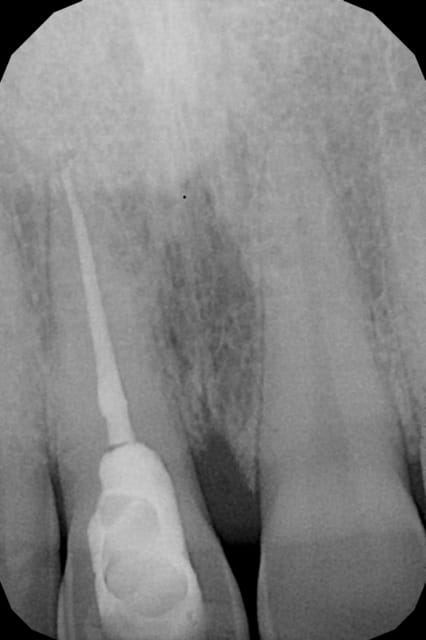

11 dévitallisée depuis longtemps et depuis une quinzaine de jours elle était douloureuse à la pression. Maintenant elle a une légère mobilité dans le sens vestibulo-palatin et une douleur quand j'appuie en vestibulaire à environ 1 cm du collet.

Est ce une fracture?

Je ne vois pas de signe de fracture visible à la radio.

Par contre t'as une lésion paro angulaire en mésiale -> qui expliquerais la palpation douloureuse proche du collet?

Au vu de la cavité d'accès, le risque de fêlure est possible.

parce que la fracture, elle est parfaitement visible sur le mien...comme je l'ai délimité en rouge....

J avais vu le même trait que toi mais même chose sur la 12...donc pas convaincu

non, c'est pas du tout la même image sur 12...enfin sur mon écran...

Possible. Honnêtement toujours pas convaincu sans vouloir te vexer.cliniquement c est tout à fait probable mais sur cette radio j aurai du mal à avoir de certitudes :-)

Un diagnostique de fracture ne peut se faire que sous différente angulation.

Sur une seul faux négatif et positif possible.

Donc convoquer le patient et faire de nouvelle radio.

le problème pour une fracture, c'est qu'il faut que l'incidence du tube RX passe pile par le trait de fracture, donc le mieux c'est pas de refaire des radios mais de faire un scan ou un cône beam

de toutes façons...les premiers signes cliniques de souffrance parodontale (abcès, fistule, ...) ne devraient pas tarder non plus si c'est bien une fracture...

L'image de départ est de tres bonne qualité, agrandissement possible à 250%

On voit bien la lésion paro... qui suit exactement le trait de fracture en zigzags (pluton)

Meme pour les presbytes / ecran moyen (!), pas de doute.

On voit bien une image paro en distal, par contre,elle ne suit pas le trajet en rouge de pluton qui est plus apical.

Donc pour moi grande probabilité de fracture,mais pas objectivable sur ce cliché ,à confirmer par la clinique

J'ai fait une nouvelle radio sous un angle un peu différent, la 1ère a été faite avec angulateur. Je lui ai presris un scan et je vous tiendrai au courant.